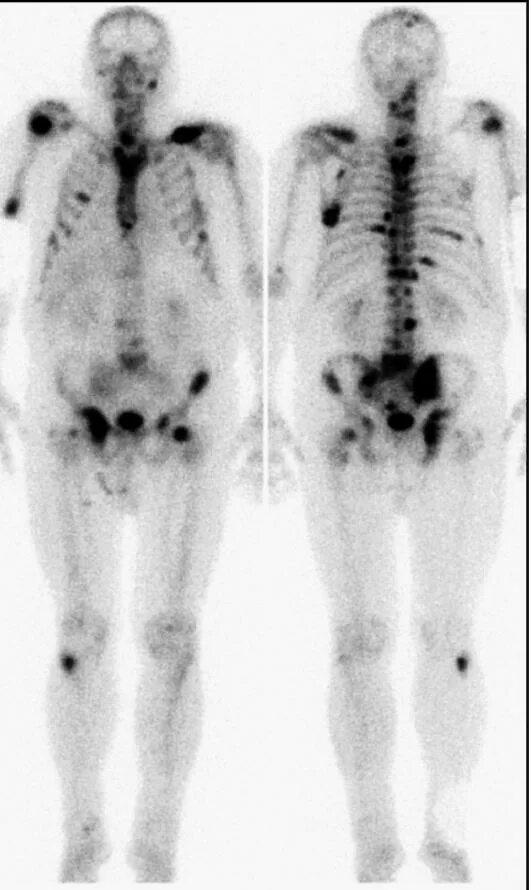

Метастазы костей скелета